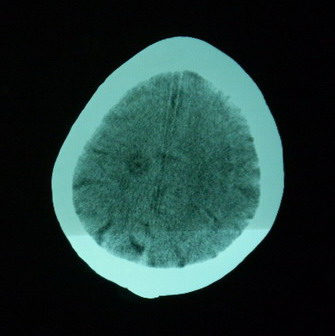

男,70岁,左侧肢体活动障碍口角向右侧歪斜2天,有高bp病史

pe:神情,能与之正常交流,吐字不清,180/90mmhg,双瞳孔无异常,左侧肢体肌力1级 b(+)

图中有个同心圆壮低密度影是ct伪影,见笑了。

1、右侧基底区及外囊区腔隙性脑梗塞。2、脑萎缩。

右基底节内囊前支区腔隙性脑梗塞,脑萎缩

支持右侧基底节区脑梗塞。

右侧基底区及外囊区腔隙性脑梗塞

右基底节区脑强隙 右基底节区低密度影密度太低 边界清 不会是2天的梗赛灶

2天左右的腔隙性脑梗死ct多难以发现 何况你的机器又差 很难显示 即使显示密度应该略低影

边缘模糊

支持腔梗。左内囊后肢亦有病灶